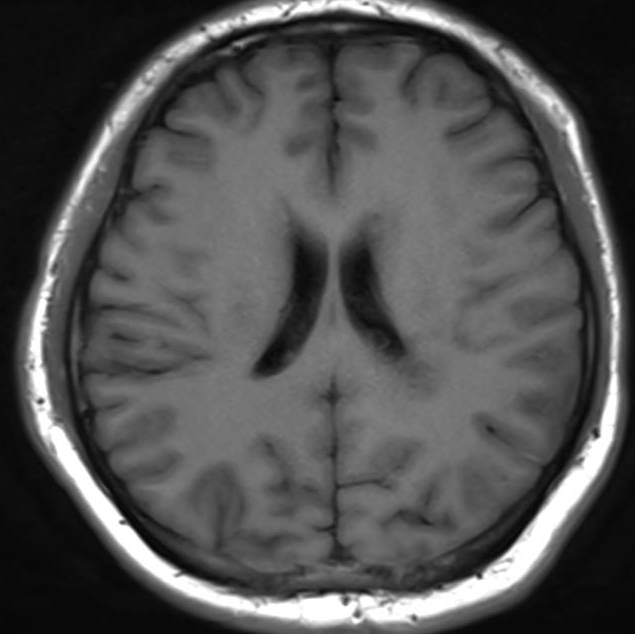

医生要求紧急做颅脑MRI,影像很快就传到了电脑上(图1-6)。医生解释,小脑蚓部占位考虑“脂肪瘤”,另有侧脑室旁白质脱髓鞘和左侧额顶叶皮质性脑炎的改变,“癫痫”可能为“继发性癫痫”。

图4 侧脑室旁病变T1WI`

图5 侧脑室旁病变T2